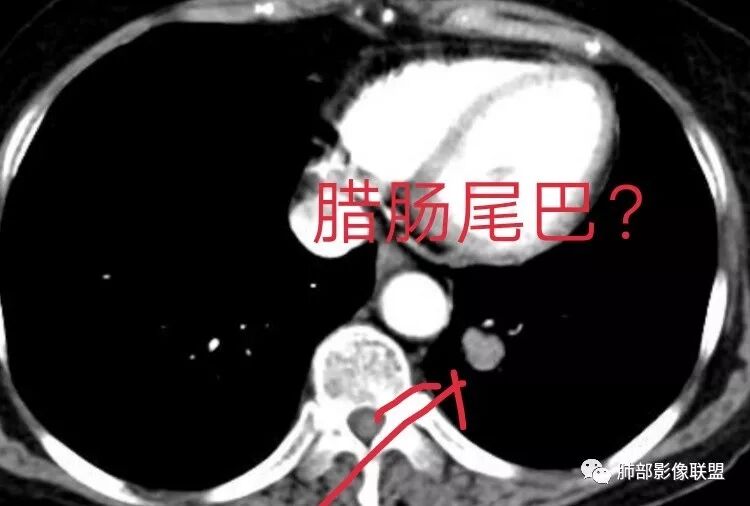

Yiren  Sishui(厶水伊人):

这个算不算腊肠尾巴?

宇宙星空:小细胞还是支气管堵塞的多吧。那个好像是血管吧。